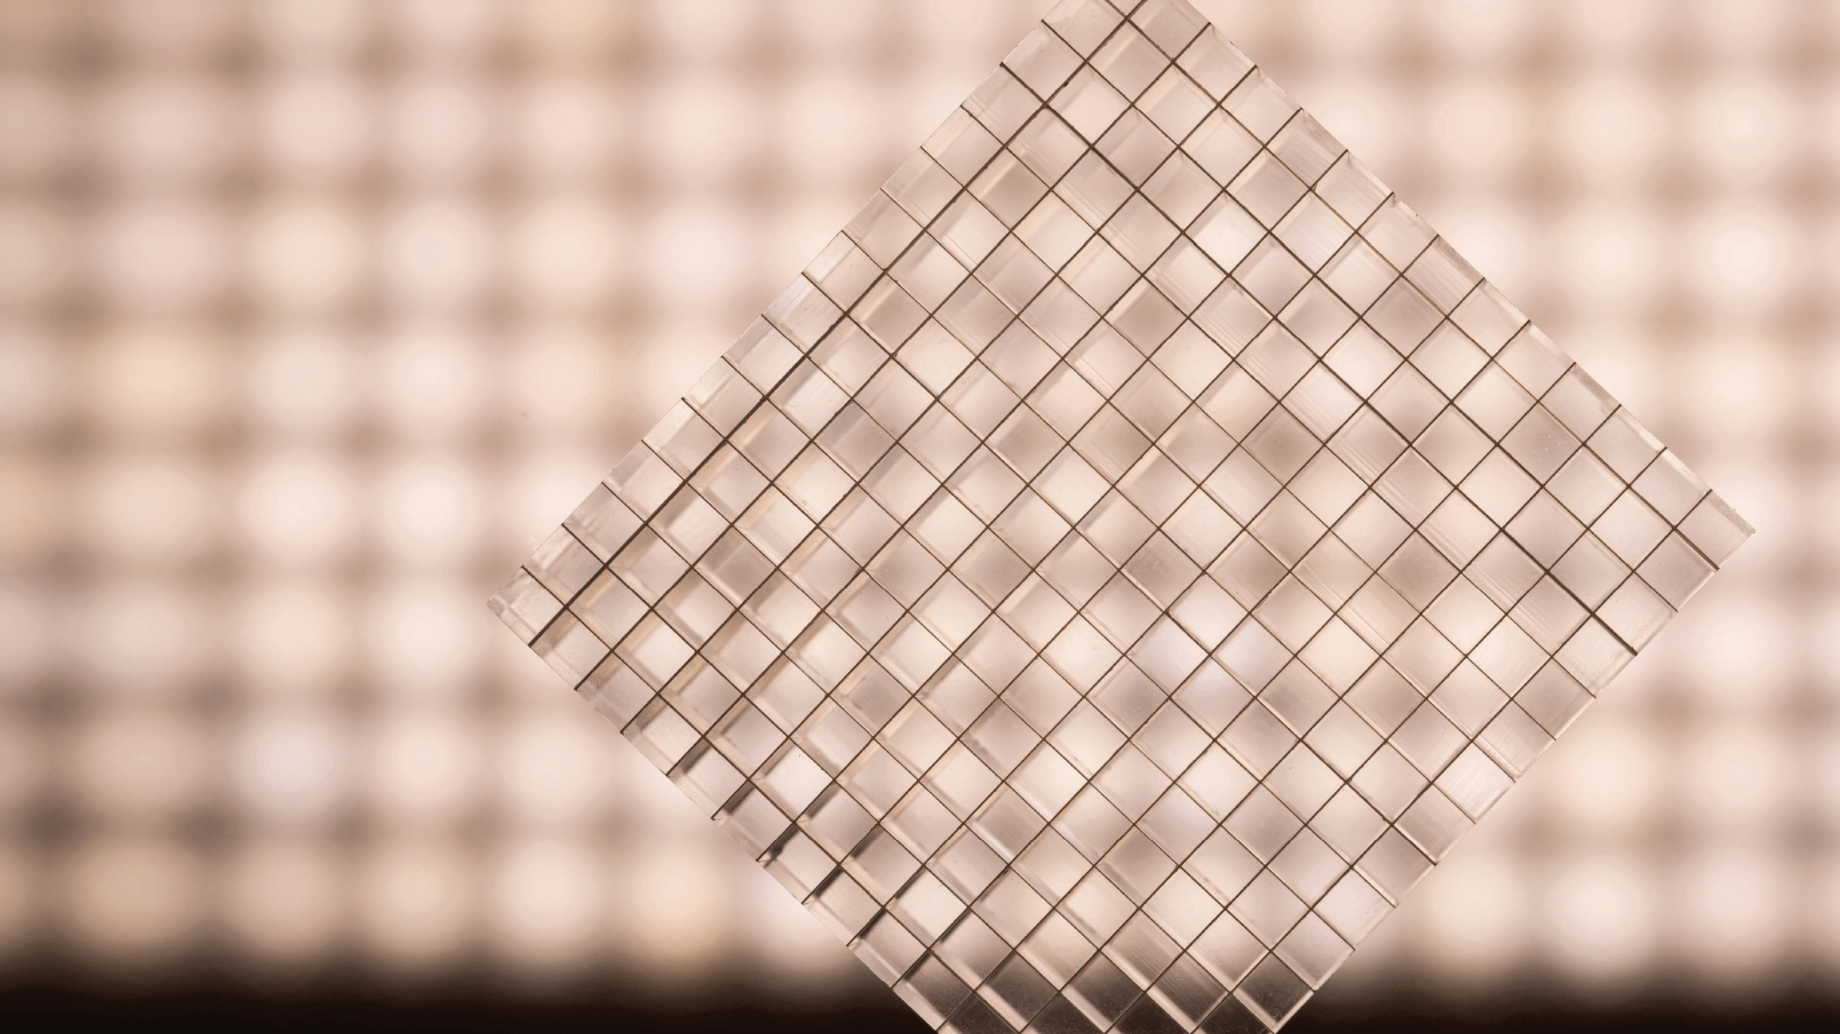

打造世界最小医用晶体

打造世界最小医用晶体

纯粹、闪烁、剔透,宛若钻石般的晶体是PET-CT中最微小却最重要的单元,作为光导探测器系统的核心组件,直接决定了整机性能与图像质量的优劣。

探测器晶体模块